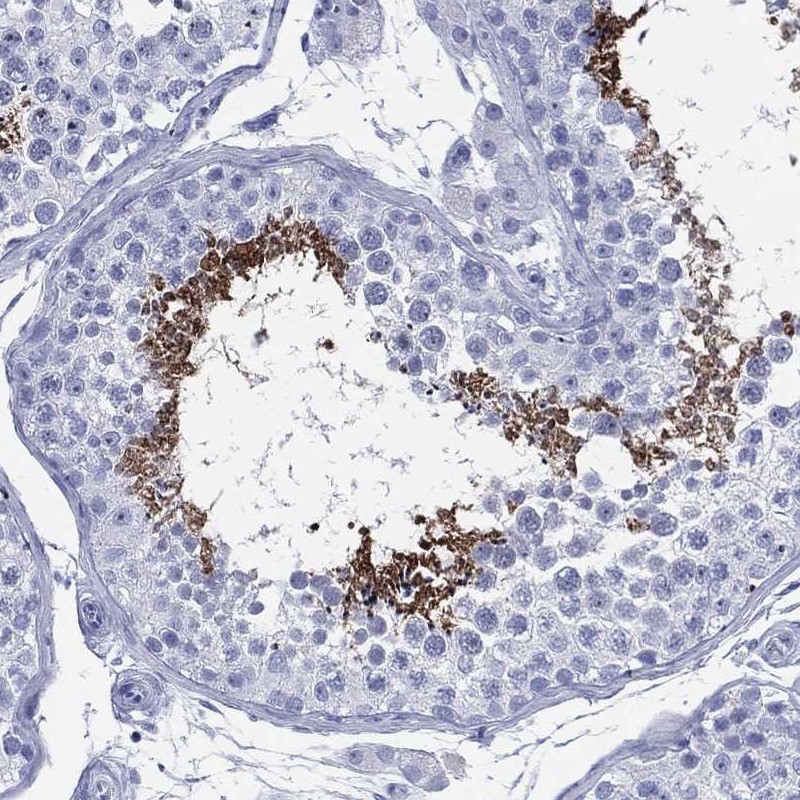

Immunohistochemical staining of human testis shows strong cytoplasmic positivity in spermatids.